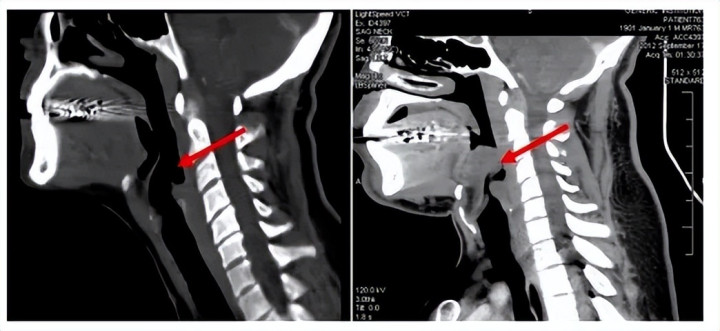

其实你不错把它相识成:喉咙口的一块“小盖子”。

平时呼吸时,它会通达,让空气奏凯相差气说念;吃饭吞咽时,它会盖下来,留心食品跑进气管。别看它小,位置却极其关节,简直守着呼吸的“命门”。

问题来了:淌若这个“小盖子”倏得发炎、肿胀,会发生什么?

谜底是——它可能像个气球相通迅速饱读起来,顺利把气说念堵死。

这等于急性会厌炎最可怕的地点。